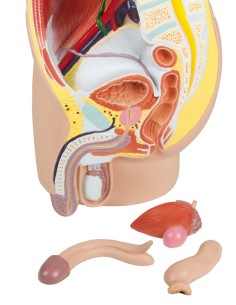

Dal cranio in 22 parti con incastri magnetici ai modelli di colonna vertebrale, da quelli di articolazioni a quelli di cuore, ogni pezzo della nostra collezione è progettato per un’immersione totale nello studio dell’anatomia umana. I nostri modelli, realizzati tramite scansioni di ossa vere, garantiscono un’esperienza tattile autentica e una fedeltà di peso quasi identica agli originali.

Essenziali per studenti e professionisti, i nostri modelli anatomici sono strumenti didattici che permettono di osservare le strutture anatomiche con precisione, eliminando la necessità di dissezioni o studi invasivi. Sono inoltre utili per spiegare ai pazienti le patologie, rendendo la comunicazione più efficace e risparmiando tempo prezioso.